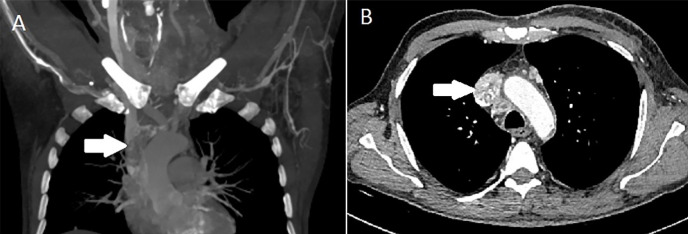

一名59岁男子入院,主诉左臂和颈部疼痛。对可能出现的颈椎脱臼进行磁共振成像检查。C7椎体可见病变伴周围骨髓水肿,与颈椎狭窄的转移相吻合。行颈椎狭窄手术,病理诊断为甲状腺癌转移灶。18f -氟脱氧葡萄糖正电子发射断层扫描/计算机断层扫描(18F-FDG PET/CT)进行进一步评估。PET/CT图像显示左颈内静脉至右心房的18F-FDG摄取增加。它被认为是恶性血栓。

A 59-year-old man admitted to the hospital complained of left arm and neck pain. Magnetic resonance imaging was performed for possible cervical discopathy. It revealed that in the C7 vertebral body, lesions with surrounding bone marrow edema were observed, which were compatible with metastasis that caused cervical stenosis. Cervical stenosis surgery was performed, and the lesion was pathologically diagnosed as a metastasis of thyroid carcinoma. 18F-fluorodeoxyglucose positron emission tomography/computed tomography (18F-FDG PET/CT) scan was ordered for further evaluation. The PET/CT images showed an increased 18F-FDG uptake from the left internal jugular vein to the right atrium. It was considered a malignant thrombus.